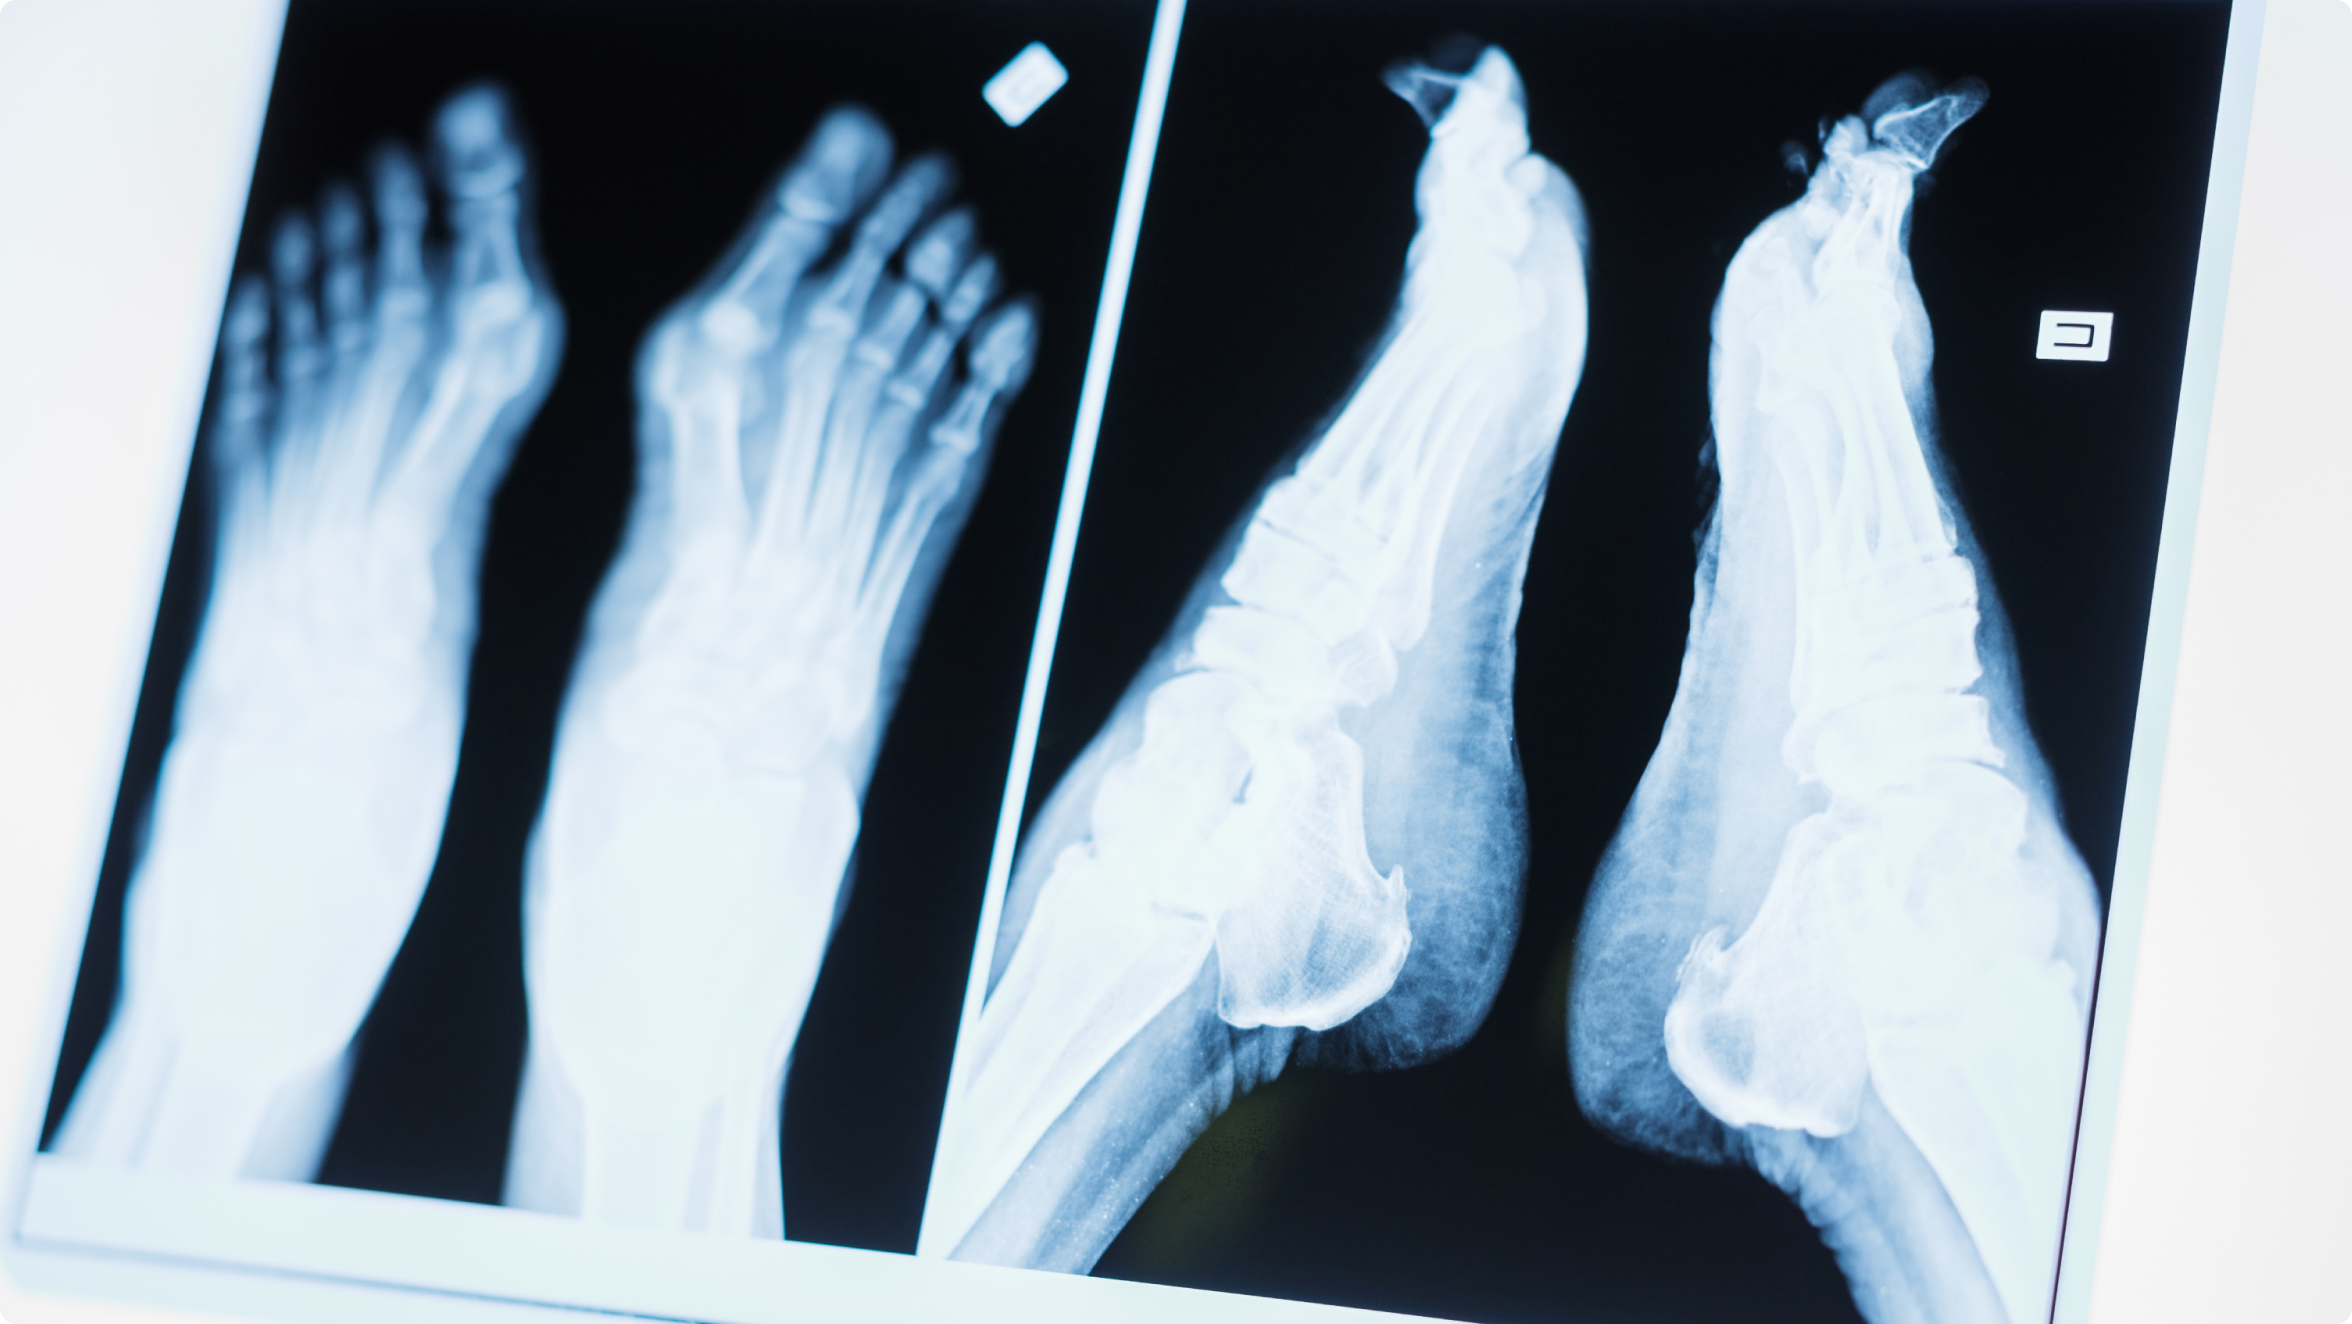

Для уточнения диагноза применяются инструментальные методы:

• УЗИ – позволяет увидеть утолщение нерва и воспалительный процесс

• МРТ – дает более детальную картину, помогает определить размеры и расположение невромы Мортона

• Рентгенография стопы – информативна для исключения других патологий и определения расстояния между головками плюсневых костей. Саму неврому Мортона на рентгене увидеть невозможно